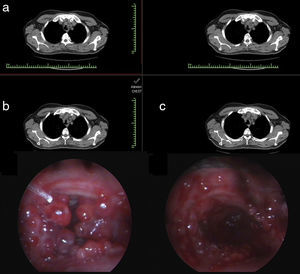

A 45-year-old man diagnosed with an atypical carcinoid tumour had undergone a left upper lobectomy completed with mediastinal lymphadenectomy. The patient was out of follow-up. He presented with dyspnoea and multiple metastases in his liver 5 years after the original diagnosis. A liver biopsy verified neuroendocrine tumour metastases, and the patient was started on everolimus. A thoracic computed tomography scan was taken (Fig. 1a). Rigid bronchoscopy revealed 3-cm long grape like nodules, starting 5cm distal to the vocal cords and obstructing the tracheal lumen 80% (Fig. 1b). The entrance to the right main bronchus and segment openings of distal bronchi were obstructed by nodular infiltrations. Nodular lesions in the trachea were coagulated with a diode laser (980nm wavelength, 4–25W, pulsed mode), and the airway was cleared. Argon plasma coagulation was used at the base of the lesions, and at the entrance of both main bronchi, to control haemorrhaging (Fig. 1c). The patient died 1 year after treatment. Survival with atypical carcinoid tumours is poor compared to typical carcinoids, but still better than for other lung cancers. Endobronchial treatment is an effective method for symptom palliation in patients with atypical carcinoid tumours and a malignant airway obstruction.